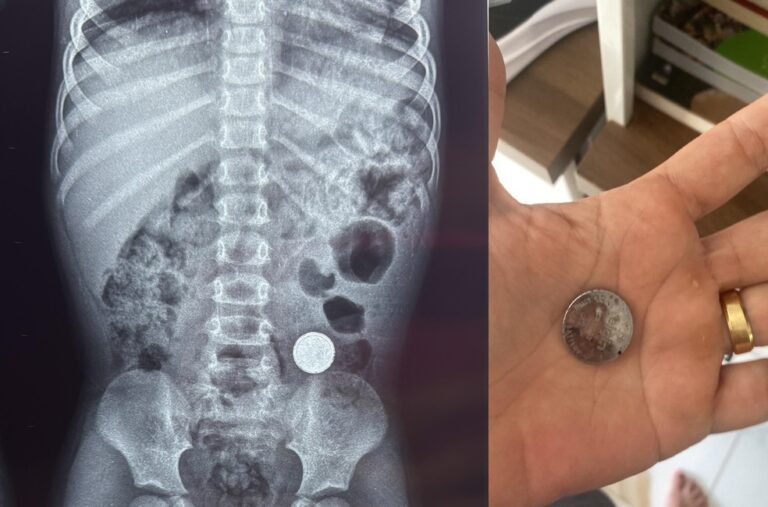

Entre os recursos já viabilizados por Cirone, para o município, estão R$ 300 mil para a revitalização e iluminação do Bosque Ministro Andreazza, R$ 280 mil para aquisição de equipamento de raio-x, R$ 106 mil para compra de medicamentos, R$ 265 mil para compra de secadores de café, R$ 85.572,00 para aquisição de implementos agrícolas, R$ 35 mil para o circuito de vaquejada, R$ 75 mil para aquisição de um trator de pneus, com carreta e grade, R$ 100 mil para aquisição de massa asfáltica e R$ 310 mil para compra de mini carregadeira.